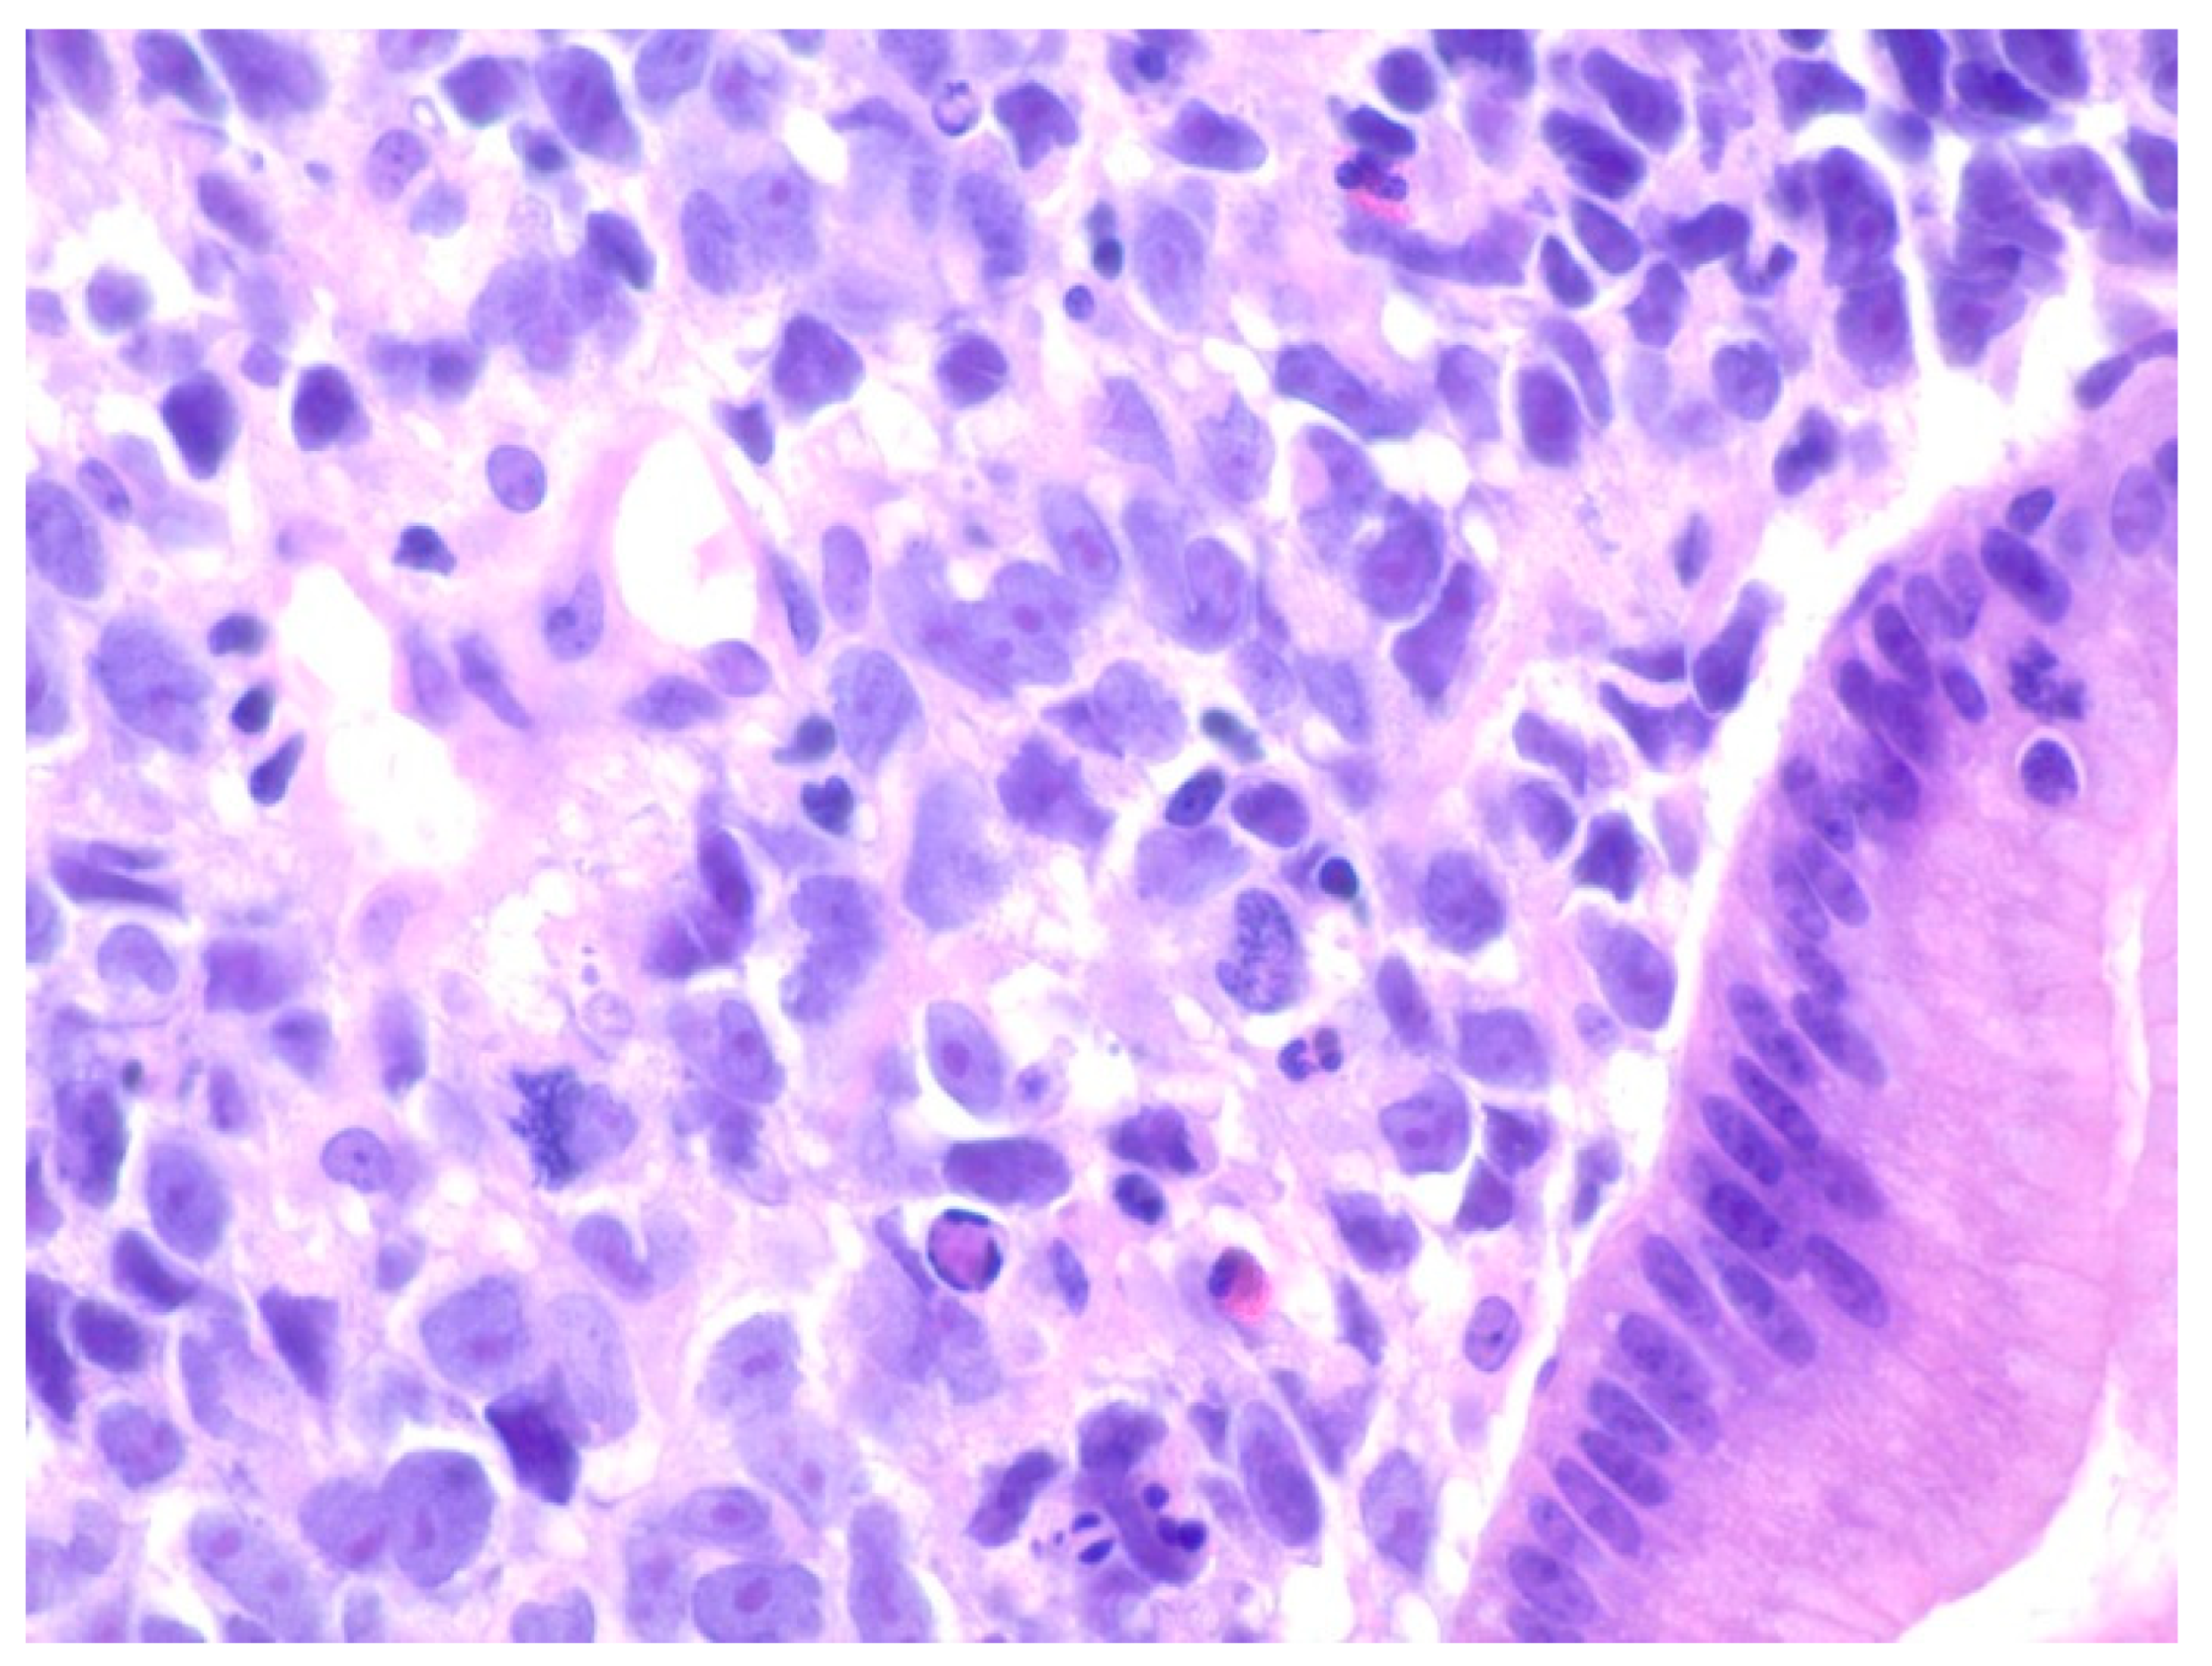

| 1 | F | 66 | Skin | Fundus, cardia, and body | Polypoid lesions with superficial ulcers | Esophagus, duodenum, mediastinum, cervical soft tissue, pancreas | Metastatic malignant melanoma | Radiotherapy and immunotherapy | Comfort care and death 5 days after EGD diagnosis of metastasis |

| 2 | M | 84 | Lymphoid | Fundus and cardia | Ulcerated and necrotic mass | Liver, urinary bladder | Diffuse large B-cell lymphoma | None | Death in 2 months after EGD diagnosis of metastasis |

| 3 | F | 35 | Lung | Fundus | Fungating mass | Esophagus, mediastinum | Large-cell neuroendocrine carcinoma | Chemotherapy-carboplatin/ etoposide | Death 1 month after EGD diagnosis of metastasis |

| 4 | F | 73 | Kidney | Fundus and body | Multiple large friable masses | Liver and lungs | Clear cell renal carcinoma | Nephrectomy, chemotherapy, immunotherapy (Axitinib) | Death 10 days after EGD diagnosis of metastasis |

| 5 | M | 76 | Lung | Body | Cratered ulcers | Liver, bone and adrenals | Small cell carcinoma (poorly differentiated neuroendocrine Ca) | None | Death 7 days after EGD diagnosis of metastasis |

| 6 | M | 61 | Lymphoid | Unknown | Clean based ulcer | None | Marginal zone lymphoma | Rituximab, Zanubrutinib, umbrasilib. OCHOP regimen currently | Progressive disease per latest scans despite therapy |